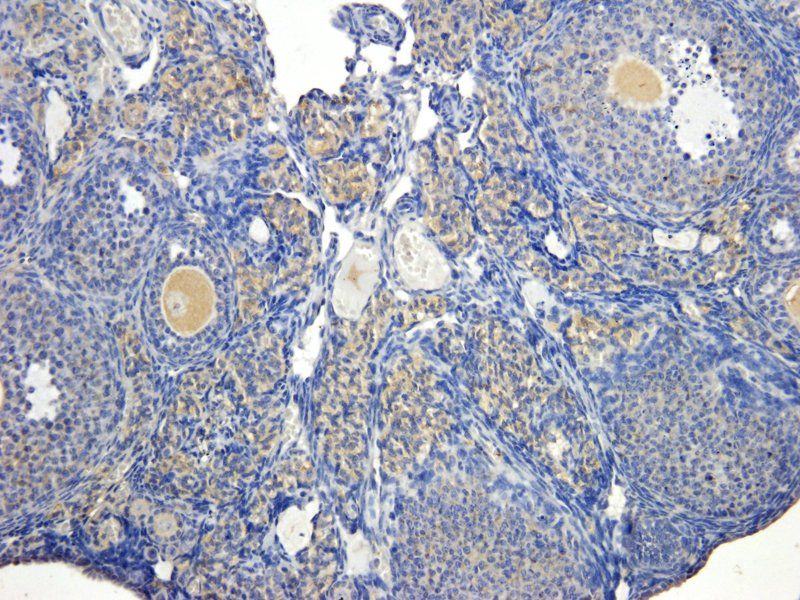

应用稀释比例:IF/ICC: 1:100, IHC-P: 1:200, WB: 1:200-1000

ELISA, ICC, IF, IHC-P, WB